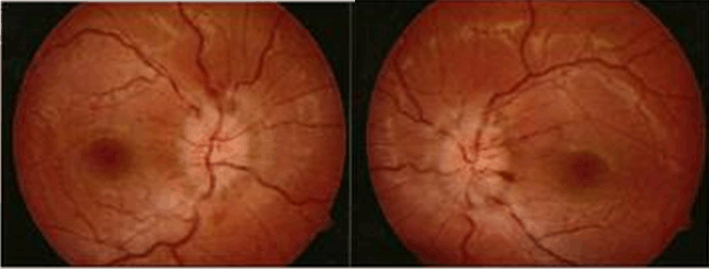

A 49-year-old woman with breast carcinoma was referred from oncology with double vision on left gaze in the last two weeks. She was diagnosed as having breast carcinoma since two years ago and was treated with chemo-radiation therapy and hormonal therapy. She complained headache, fever and severe vomiting. History of head trauma and decrease of visual acuity were denied. Ophthalmic examination showed best corrected visual acuity were 20/25 in both eyes, anterior segment was within normal limits. There was restriction in abduction on left eye corresponding to abducens nerve palsy (Figure 1). Posterior segments (funduscopy) of both eyes were normal (Figure 2A). We diagnosed her with left abducens nerve palsy. Non-contrast head Computed Tomography (CT) scan on axial slice showed hyperdense lesion with irregular firm edges, sized 2x1cm in the right frontal lobe and 2x2,4cm in the right parietal lobe. The lesion spreads and destructs the right frontal and parietal bones. CTScan result suggested intracranial and bone metastasis (Figure 2B).

Figure 2: (A) Funduscopy photographs of the patient showed normal posterior segments on both eyes. (B) Hyperdense lesion with irregular firm edges, sized 2x1cm in the right frontal lobe and 2x2.4 cm in the right parietal lobe (arrow).